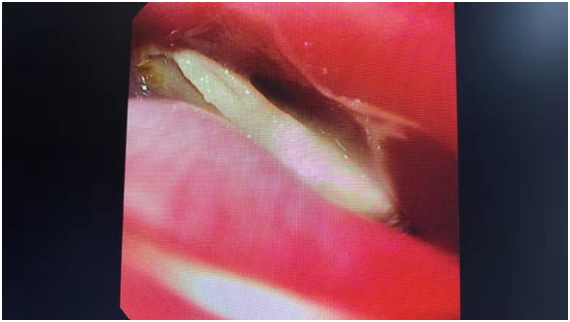

(胃鏡下“元兇”現(xiàn)身)

第二天一早,一夜寢食難安的張女士再次來到仁慈消化內(nèi)鏡室。經(jīng)過麻醉,在胃鏡直視下,潘主任準(zhǔn)確地找到了異物,慢慢將這根在食管壁內(nèi)卡著的雞骨頭順利取出。整個操作過程中,食管沒有受到任何的拉傷。

看到躺在紗布上長約3厘米的“V”形雞骨頭,張女士驚嘆:“我怎么吞下去的呀?”

(取出的“V”形雞骨頭,大約3厘米長)